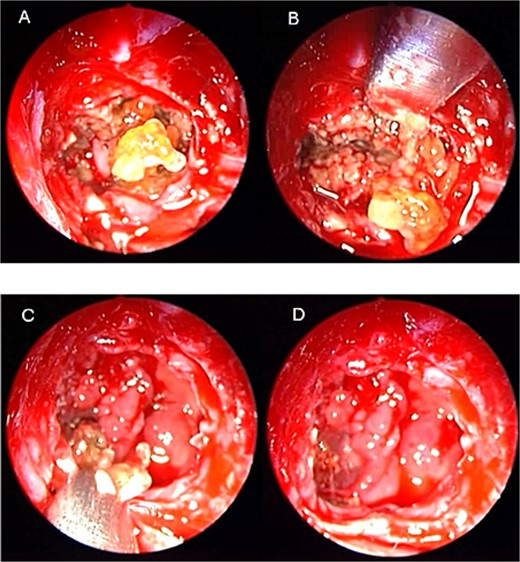

A 69-years-old diabetic female was referred from neurology as she complained of an acute onset severe headache, diplopia, and retro-orbital pressure. An initial CT scan with a subsequent MRI scan (Fig. 5) showed infiltrative sphenoid pathology invading both skull base and cavernous sinus given a provisional diagnosis of acute invasive fungal sinusitis. The patient was urgently taken to the operative theater to endoscopically debride sphenoid sinuses (Fig. 6). Histopathological examination confirmed the diagnosis of invasive sphenoid sinus mucormycosis.

Coronal CT (A) and MRI (B) and CT image guided intra-operative (C) images of the paranasal sinuses showing aggressive sphenoid sinus disease extending to the skull base and cavernous sinus.

Intra-operative endoscopic view of shenoid sinus debridement of invasive fungal disease.